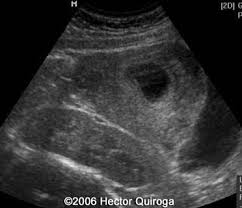

Ultrasound Kidney Upper Pole. Transverse a and longitudinal b views of the left kidney show a dilated obstructed upper pole collecting system and proximal ureter u. What is a questionable punctate calcific density in the kidney ct report says that.

Angiomyolipoma seen as a hyperechoic mass in the upper pole of an adult kidney. Figures 5 2 and 5 3 demonstrate the anatomic position of the right and left renal unit. Renal ultrasound us is a common examination which has been performed for decades.